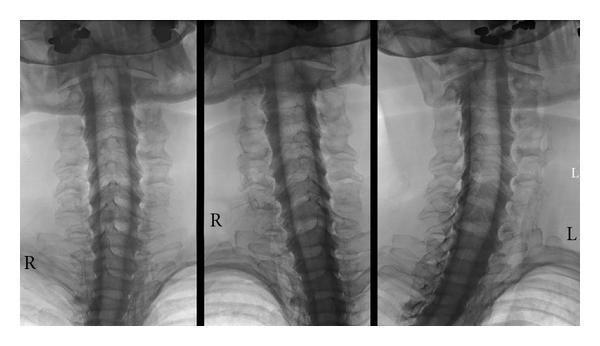

Setelah injeksi, pencitraan sinar-X waktu nyata (fluoroskopi) dilakukan. Pewarna kontras yang disuntikkan membantu menyorot dan membedakan jaringan lunak di tulang belakang sehingga jaringan lunak ini muncul dengan baik dalam pencitraan yang dihasilkan, yang disebut myelogram. Myelography sangat berguna dalam menunjukkan kasus kompresi akar saraf, bahkan pada kasus yang halus.

Dalam banyak kasus, CT scan dilakukan setelah myelography untuk memberikan gambaran rinci tentang tulang dan jaringan lunak. Misalnya, seperti MRI dengan dan tanpa kontras, CT myelogram biasanya digunakan untuk mengevaluasi nyeri leher dan/atau punggung kronis setelah operasi tidak berhasil.

- Gambar diambil dan direkam menggunakan fluoroskopi atau CT scan.

Setelah menyelesaikan tes myelography, ahli radiologi akan melakukan CT scan untuk lebih memahami penyebab gejala. Ahli radiologi kemudian akan mengirimkan laporan terperinci ke dokter yang merawat kamu.